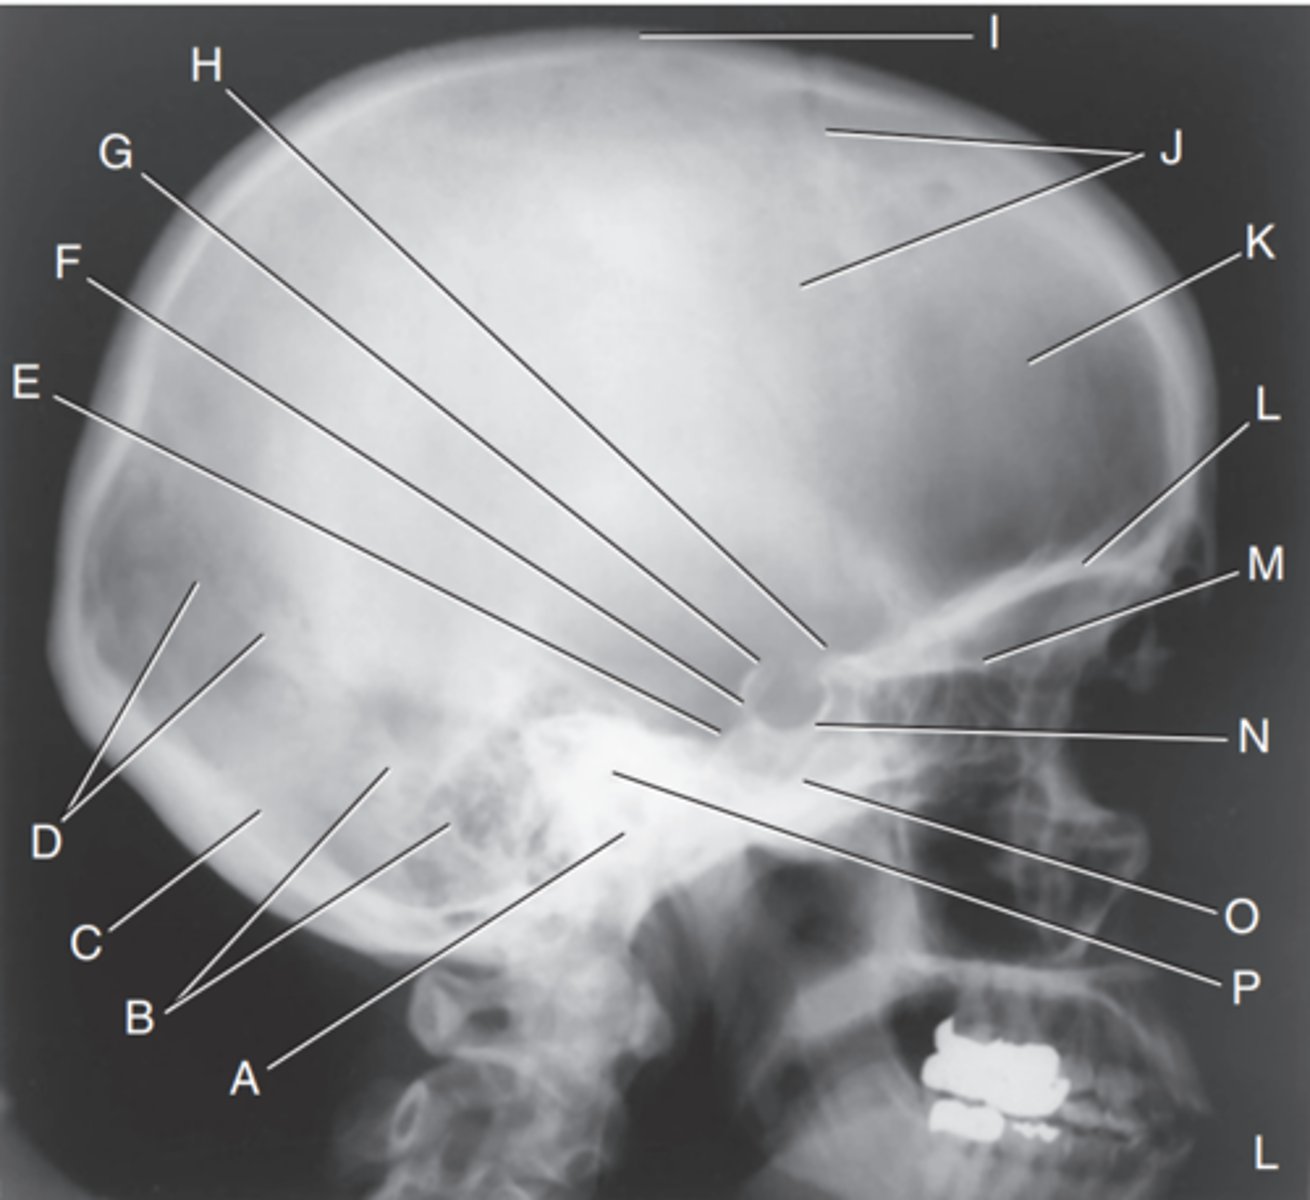

EAM

Label A

Mastoid portion of temporal bone

Label B

Occipital bone

Label C

Lambdoidal suture

Label D

Clivus

Label E

Dorsum sellae

Label F

Posterior clinoid processes

Label G

Anterior clinoid processes

Label H

Vertex of cranium

Label I

Coronal suture

Label J

Frontal bone

Label K

Orbital plates

label L

Cribriform plate

Label M

Sella turcica

Label N

Body of sphenoid (sphenoid sinus)

Label O

Petrous portion of temporal bone

Label P